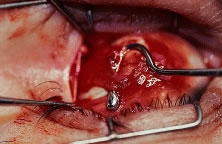

RECESSION PROCEDURE: FORNIX INCISION

This procedure is recession of the right medial rectus muscle. The eyelids are separated with a Barraquer open-blade wire eyelid speculum (Fig. 8). The open-blade design provides more room for exposure and makes it easier to pass the suture needles, especially in small children or when large recessions are performed. The globe is grasped with a Lester forceps at the limbus. It is best to grasp the limbus with the forceps held perpendicular to the globe and then to position the forceps so that they are rotated and lie tangential to the globe. Forced ductions are performed to detect any restriction of movement of the globe (Fig. 9).

The globe then is gently elevated from the orbit or proptosed at the same time it is abducted or adducted to prepare for the incision. Elevation of the globe helps to separate the horizontal rectus muscle from the inferior rectus muscle so that the inferior rectus muscle is not cut when the incisions are made. The conjunctiva is grasped by the assistant with a Manhattan toothed forceps (Fig. 10). This forceps has teeth that are angled outward and are designed to grasp conjunctiva, as well as the deeper subconjunctival tissue, so that when the blunt-tipped Westcott scissors cuts into the tented tissue, an incision is made into the conjunctiva and Tenon's capsule (Fig. 11A and B). If the incision does not completely penetrate Tenon's capsule and the intermuscular septum to the scleral surface of the eye, additional tissue (anterior Tenon's tissue and/or intermuscular septum) is grasped with the Manhattan forceps and at least one additional cut is made.

A Stevens' tenotomy hook is passed by the surgeon into the incision and is rotated so that it can be slid underneath the muscle insertion with the tip of the hook held tangential to the globe (Fig. 12). The hook should be passed 2 to 3 mm posterior to the expected location of the muscle insertion. Care is taken not to incorporate intramuscular septum or other adventitial tissue on the hook. When the lateral rectus muscle is secured with the Stevens' or Jameson muscle hook, care should be taken not to bring the inferior oblique muscle up to the insertion (Fig. 13). When the muscle is secured with the Stevens' hook, the hook and the inferior edge of the muscle insertion are elevated and a Jameson muscle hook is passed between the tented muscle tissue and the sclera to secure the muscle at its insertion (Fig. 14). Care is taken to include the entire insertion of the tendon on the hook. The tip of the Jameson hook is gently elevated by depressing the heel of the hook. This maneuver helps to ensure that the entire tendon of the muscle remains captured on the hook. A Stevens' tenotomy hook is placed in the incision, this time anterior to the insertion beneath the conjunctiva (Fig. 15). The Stevens' hook is passed posterior over the orbital surface of the muscle (Fig. 16). Gentle pressure on the Stevens' hook is directed posterior so that the check ligaments and Tenon's tissue that overlie the muscle belly are separated from the muscle capsule with blunt dissection. The hook usually is passed posterior for about 10 mm. When recessing a lateral rectus, attachments between the underside of the lateral rectus and inferior oblique are broken (Fig. 17). Two or three passes over the muscle are made, and, with simultaneous countertraction on the Stevens' hook and the Jameson hook, the conjunctiva is elevated and pulled over the tip of the Jameson hook (Fig. 18A and B).

|

The intermuscular septum and Tenon's capsule at the ball-like tip of the Jameson hook are incised with a Westcott scissors (Fig. 19). A Manhattan forceps can be used to elevate the intramuscular and Tenon's tissue to facilitate this step. Care is taken to incorporate the entire muscle tendon on the Jameson hook before this cut is made. If it is evident that there is residual tendon that is not placed on the hook, the additional tendon, intramuscular septum, and anterior Tenon's tissue are reflected over the tip of the Jameson hook with the closed tips of the Westcott scissors or a small muscle hook.

A Stevens' hook is inserted in the opening in the intermuscular septum created by the scissors and is passed anterior to the insertion. Parks has referred to this maneuver as the “pole test.” This maneuver is done to verify that the tendon of the muscle has not been split and that the complete muscle tendon is incorporated on the hook. Leaving residual slips of muscle tendon will partially or completely negate the effect of a recession procedure (Fig. 20A and B).

The anterior Tenon's capsule is cut free from the muscle insertion by grasping the loose tissue anterior to the insertion of the tendon with a forceps and gently tenting it (Fig. 21A and B). Care is taken not to grasp muscle capsule or muscle tendon fibers in the forceps. To best accomplish this step, the blunt tipped Westcott scissors is placed perpendicular to the globe. Cleaning the tissue anterior to the muscle permits passing the needle accurately through the rectus muscle tendon with unobstructed visualization. If the capsule of the muscle tendon is cut, the tendon may split. Two small Stevens' hooks are used to elevate the conjunctiva and expose the intermuscular septa and the tissue overlying the muscle capsule. These tissue bands are cut with the Westcott scissors (Fig. 22A and B). Care is taken not to cut into the muscle or the capsule of the muscle (Fig. 23). The intermuscular septa can be cut 3 to 4 mm back for recessions and 5 to 9 mm back for resections.42

The tendon of the rectus muscle is elevated by lifting it away from the globe with the Jameson hook in a plane that is perpendicular to the surface of the globe. With gentle traction on the muscle insertion with the Jameson hook, a fine spatulated needle with a synthetic absorbable suture is woven through the tendon 1 mm from its insertion to the globe (Fig. 24). The needle exits at the superior edge of the muscle tendon and is then passed back underneath the tendon of the muscle (Fig. 25A and B). The needle is then passed back through the tendon from underneath (lock bite) and out the anterior surface of the tendon, taking a 2-mm portion of tendon that will be incorporated into the double-lock knot. Taking too large a lock bite will tend to narrow the width of the muscle tendon (Fig. 26A and B). The two sutures are brought up and held by the surgeon's thumb on the frets of the Jameson hook (Fig. 27). A blunt-tipped Westcott scissors is used to cut the muscle tendon free from its insertion. The cutting blade of the Westcott scissors is passed posterior to the muscle insertion. Care is taken not to push the tip of the scissor into the insertion but rather to pass the posterior tip of the scissor behind the muscle tendon, in the free space created by elevating the muscle with the Jameson hook. Two or three snips usually are required to remove the muscle from the globe. Care is taken to cut the scleral portion of the insertion flush with the globe. Leaving a large stump at the old insertion will leave a vertical white band of tissue that will show through the conjunctiva and leave an unsightly scar.

|

|

The muscle is suspended to verify that both the muscle tendon and the muscle capsule are incorporated with the suture and its lock bites (Fig. 28). In addition, pulling the sutures superior and inferior will assure the surgeon that the transverse suture that was woven through the tendon was not cut when the muscle was removed from the globe (Fig. 29).